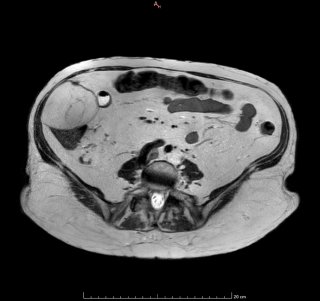

Case presentation

We report the case of a 17-year-old previously healthy male who developed sudden severe dyspnea while recreational skiing at a moderate altitude of 2'200 meters. On-site emergency management required immediate bilateral needle decompression, followed by urgent transfer to hospital care. Imaging confirmed a complete bilateral pneumothorax with bilateral apical subpleural blebs (Figure 1). Sequential bilateral chest tube placement was performed, and the patient subsequently underwent staged bilateral video-assisted thoracoscopic surgery with apical wedge resection and mechanical pleurodesis. Postoperative recovery was uneventful, with no recurrence during follow-up. Etiological investigations revealed normal alpha-1 antitrypsin levels. Transthoracic echocardiography identified a bicuspid aortic valve associated with moderate aortic regurgitation (grade 2/4). Combined clinical, radiological, and cardiac findings ultimately led to the diagnosis of Marfan syndrome, previously unrecognized.